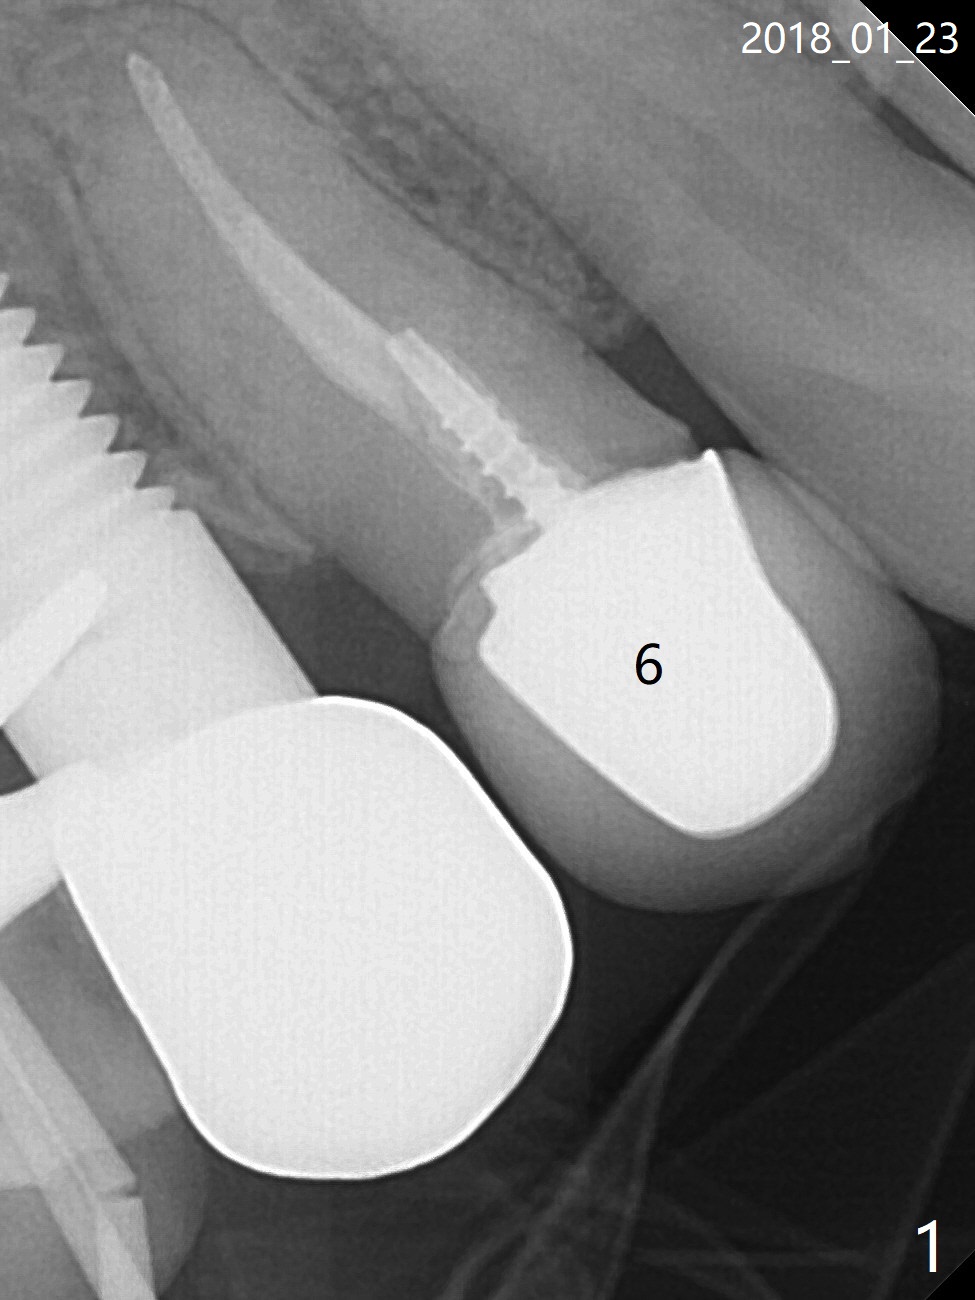

A 56-year-old woman has dislodged #6 crown/post twice in the last 10 years (Fig.1). The root appears to fracture (Fig.2 <), as related to the post (P) and large periapical radiolucency (*). A 3.8x13 mm implant will be placed (Fig.3). PRF membrane and Sticky bone will be inserted while the last drill is in place. Section the root for socket shield. Prepare gingival protection instrument. Reanalysis of CT reveals that the root palatally (Fig.4 *) may cause resorption (<) of the thick palatal plate. The root fracture is supported by profilogram (Fig.5). Therefore the implant should be placed deeper (Fig.6) than that in Fig.3 and shorter if a straight abutment is going to be used (blue (pink: cuff)). In fact the socket is intact when the tooth is extracted. The crown is loose because of post fracture.